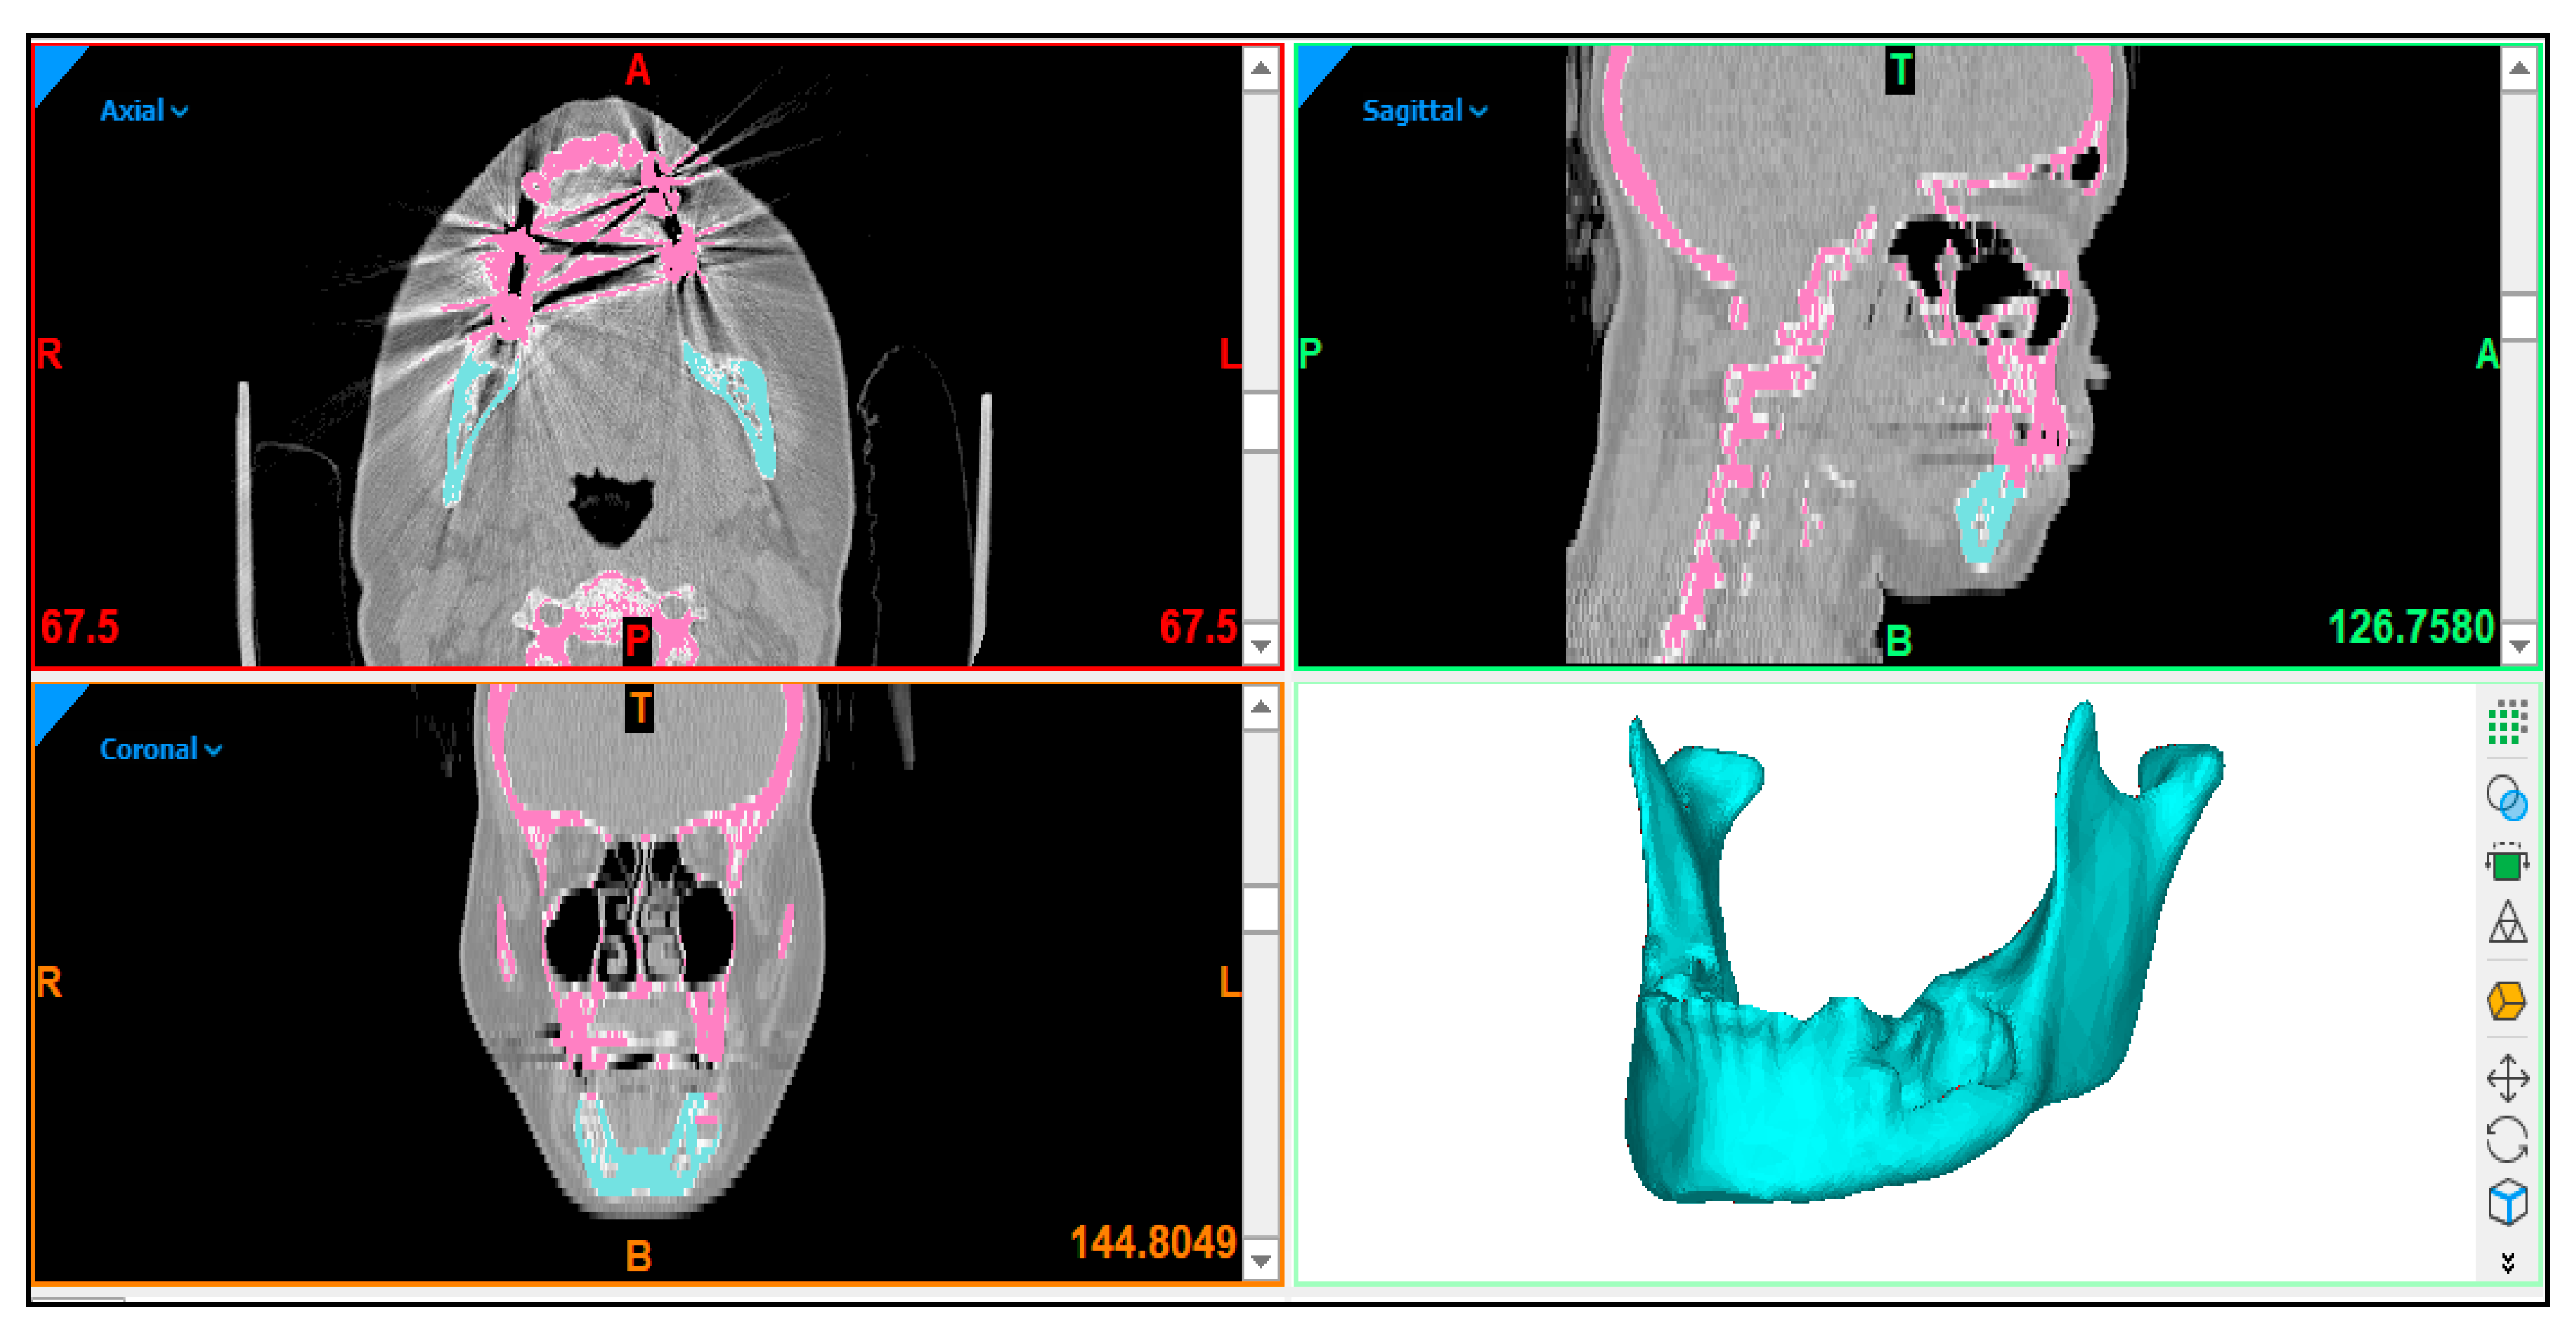

2.2. Image Acquisition and Processing

2.3. Custom Implant Design